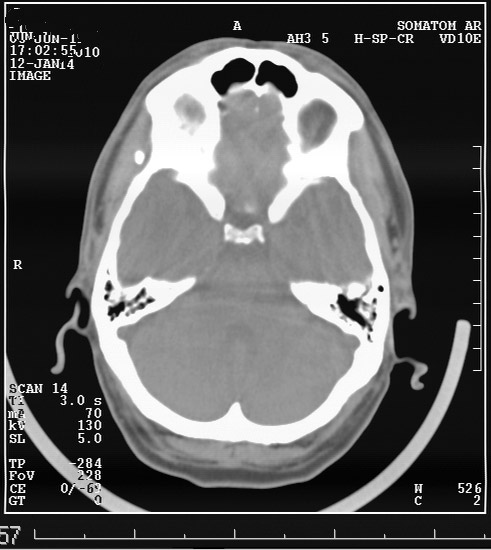

Выкладываю данные КТ

На снимке утолщение веретенообразное мышечного слоя с наличием кальцификатов(два) Кальцификаты в мышце чаще встречаются при паразитарных инфекциях(трихиниллез,токсоплазмоз,цистецеркоз),но их больше по количеству и в разных местах.Оссифицирующий миозит-имеет свою картину и распространение.Насчет Хортона-навряд ли,это же поражение сосуда.Насчет тофусов-они содержат ураты,чаще локализуются подкожно(не в мышце),при подагре осификации вдоль сухожилий.А может был удар,гематома с частичной кальцификацией?